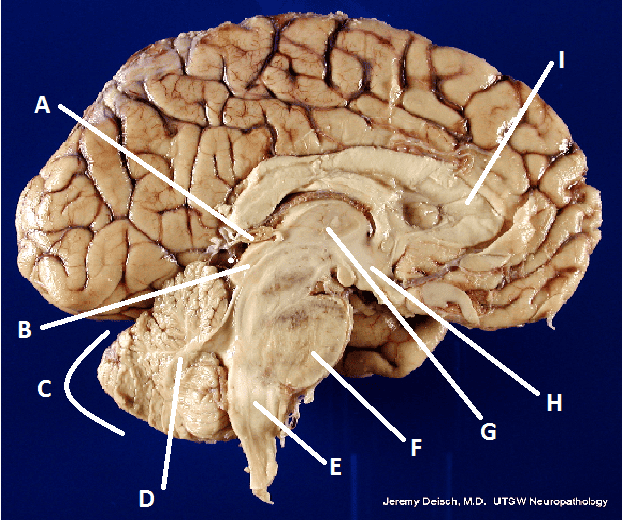

What is A?

Pineal body (gland)

What is B?

Hypothalamus

What is C?

Cerebellum

What is D?

Arbor Vita

What is E?

Medulla Oblongata

What is F?

Pons

What is G?

Thalamus

What is I?

Corpus Callosum